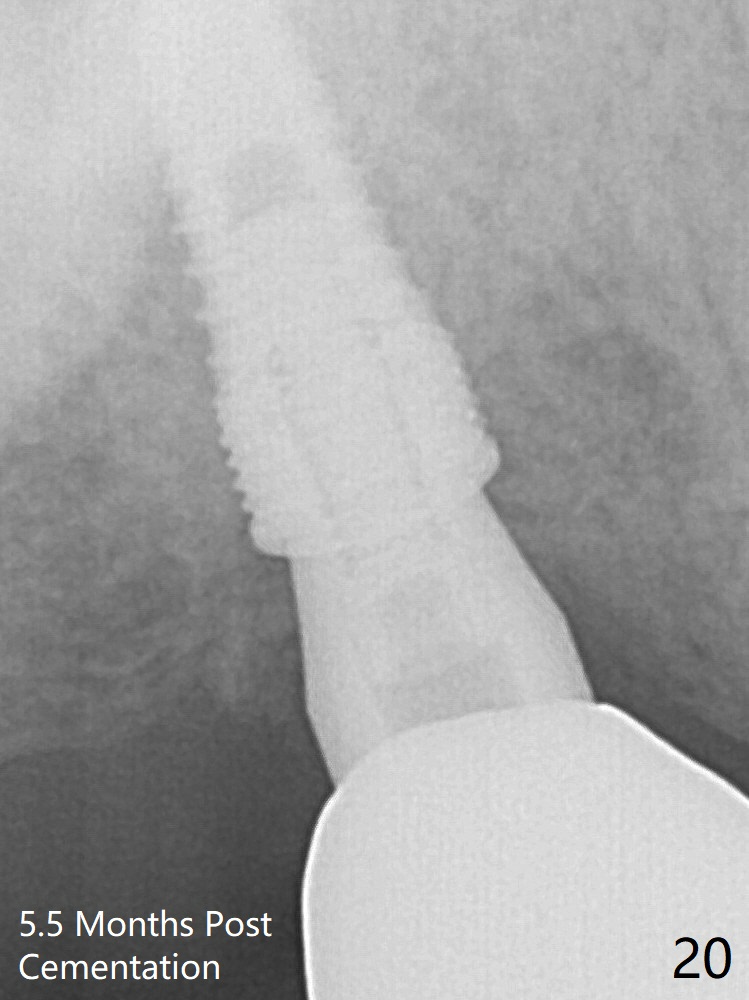

The 4.5x10 mm SM implant appears to have penetrated the sinus floor for primary stability (Fig.7 red dashed line).  *: bone graft around the coronal portion and the implant and the apical portion of the abutment (6.8x5.5(6) mm).  There is no loss of bone graft 3 months postop (Fig.16 (abutment: 4.8x7(4.5) mm)).  The bone density around the coronal implant appears to increase 5.5 months post cementation (Fig.20).